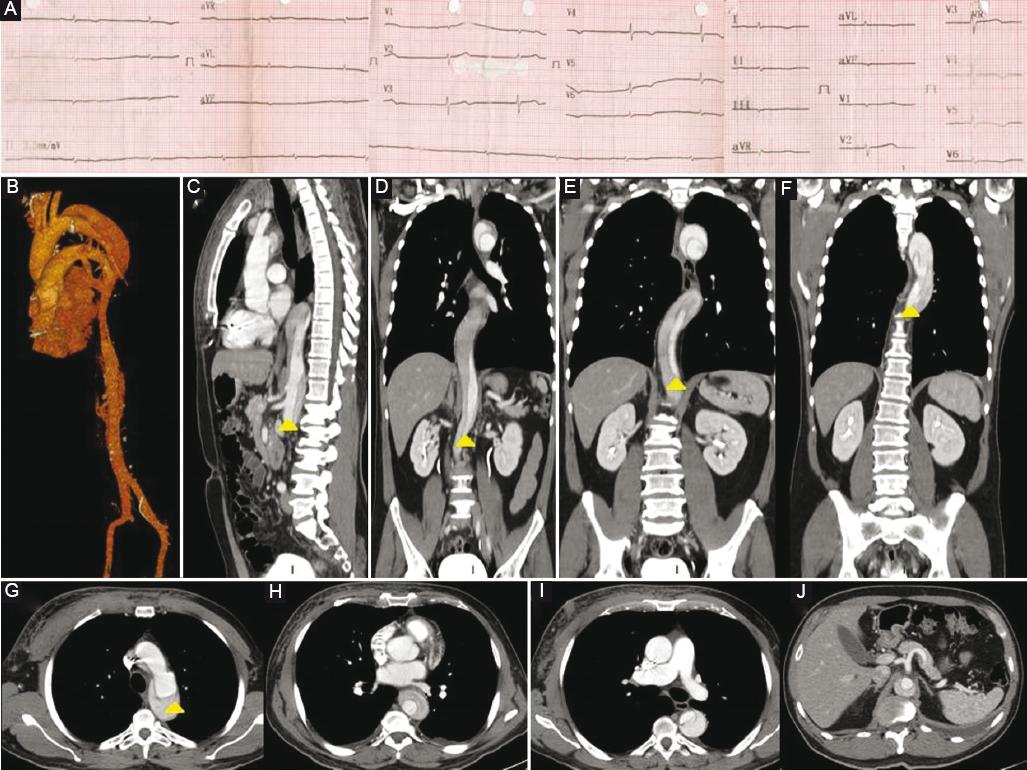

A 59-year-old male with a history of hypertension for 15 years, with inadequate treatment, had chest pain and diaphoresis, for more than 20 min. He went for medical attention at an ambulatory clinic where he was diagnosed with an hypertensive crisis and received an angiotensin-converting enzyme inhibitor. He was referred to a hospital and at his arrival, physical examination was normal, and the electrocardiogram revealed a first-degree AV block so he was discharged home with medical treatment. One day later, the patient had recurrence of symptoms and returned to the emergency room. Vital signs at this arrival were blood pressure 184/79 mmHg, heart rate 58 beats/min, respiratory rate of 19 rpm, temperature 37°C, weight 81 kg, height 1.70 m, and peripheral pulses which were augmented in intensity in all extremities. The electrocardiogram showed a complete AV block (Fig. 1A) and asymmetric T-wave inversion in V4-V6. He underwent measurement of troponin which was positive. The initial medical treatment included aspirin, nitrates, anticoagulation, beta-blocker, calcium channel blocker, and high-intensity statin. Given the difficulty to maintain blood pressure goals, he received nifedipine. Due to his heart rhythm, a definitive pacemaker was placed in DDDR modality. He persisted with blood pressure >160/100 mmHg and chest pain despite medication. Due to this situation, he was taken to coronary angiography through femoral access, but the study was incomplete due to inability to introduce the catheter through the aorta. On aortography, the diagnosis of aortic dissection Stanford A and Debakey I was made and then confirmed through computed tomography (CT) scan (Fig. 1B: three-dimensional reconstruction of aorta. Fig. 1C-J: axial views). Intravenous nitroprusside was initiated and the patient was referred for surgical treatment.

Figure 1 A: Electrocardiogram showing complete atrioventricular block. B: Aortic three-dimensional reconstruction. C: Computed tomography (CT) sagittal view showing aortic dissection. D: CT frontal view showing aortic dissection in the abdominal aorta. E: CT frontal view showing aortic dissection in the thoracic and abdominal aorta. F: CT frontal view showing aortic dissection in the thoracic aorta. G: CT axial view showing aortic dissection and flap in the ascending thoracic aorta. H: CT axial view showing aortic dissection in the descending aorta. I: CT axial view showing aortic dissection in the descending aorta and pacemaker electrode. J: CT axial view showing aortic dissection in the descending aorta without involvement of the mesenteric arteries.